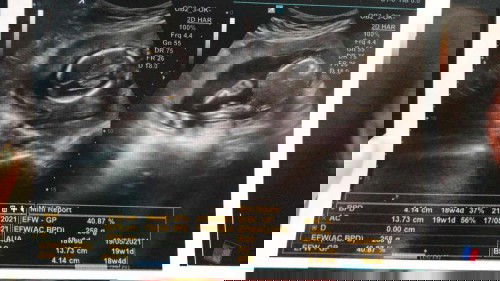

USG 19w Yang Membahagiakan

alhamdulillah 22 Desember 2020 kemarin aku USG perasaan aku Deg degan dan exited banget karena pengen melihat adek, karena udah 2 bulan gak tenggok. ketika di USG bersyukur banget ukuran dan air ketuban bagus. semoga dedek berkembang dengan baik, Sehat terus dan Jadi anak yang Sholeh sholehah ❤️ aminnn...